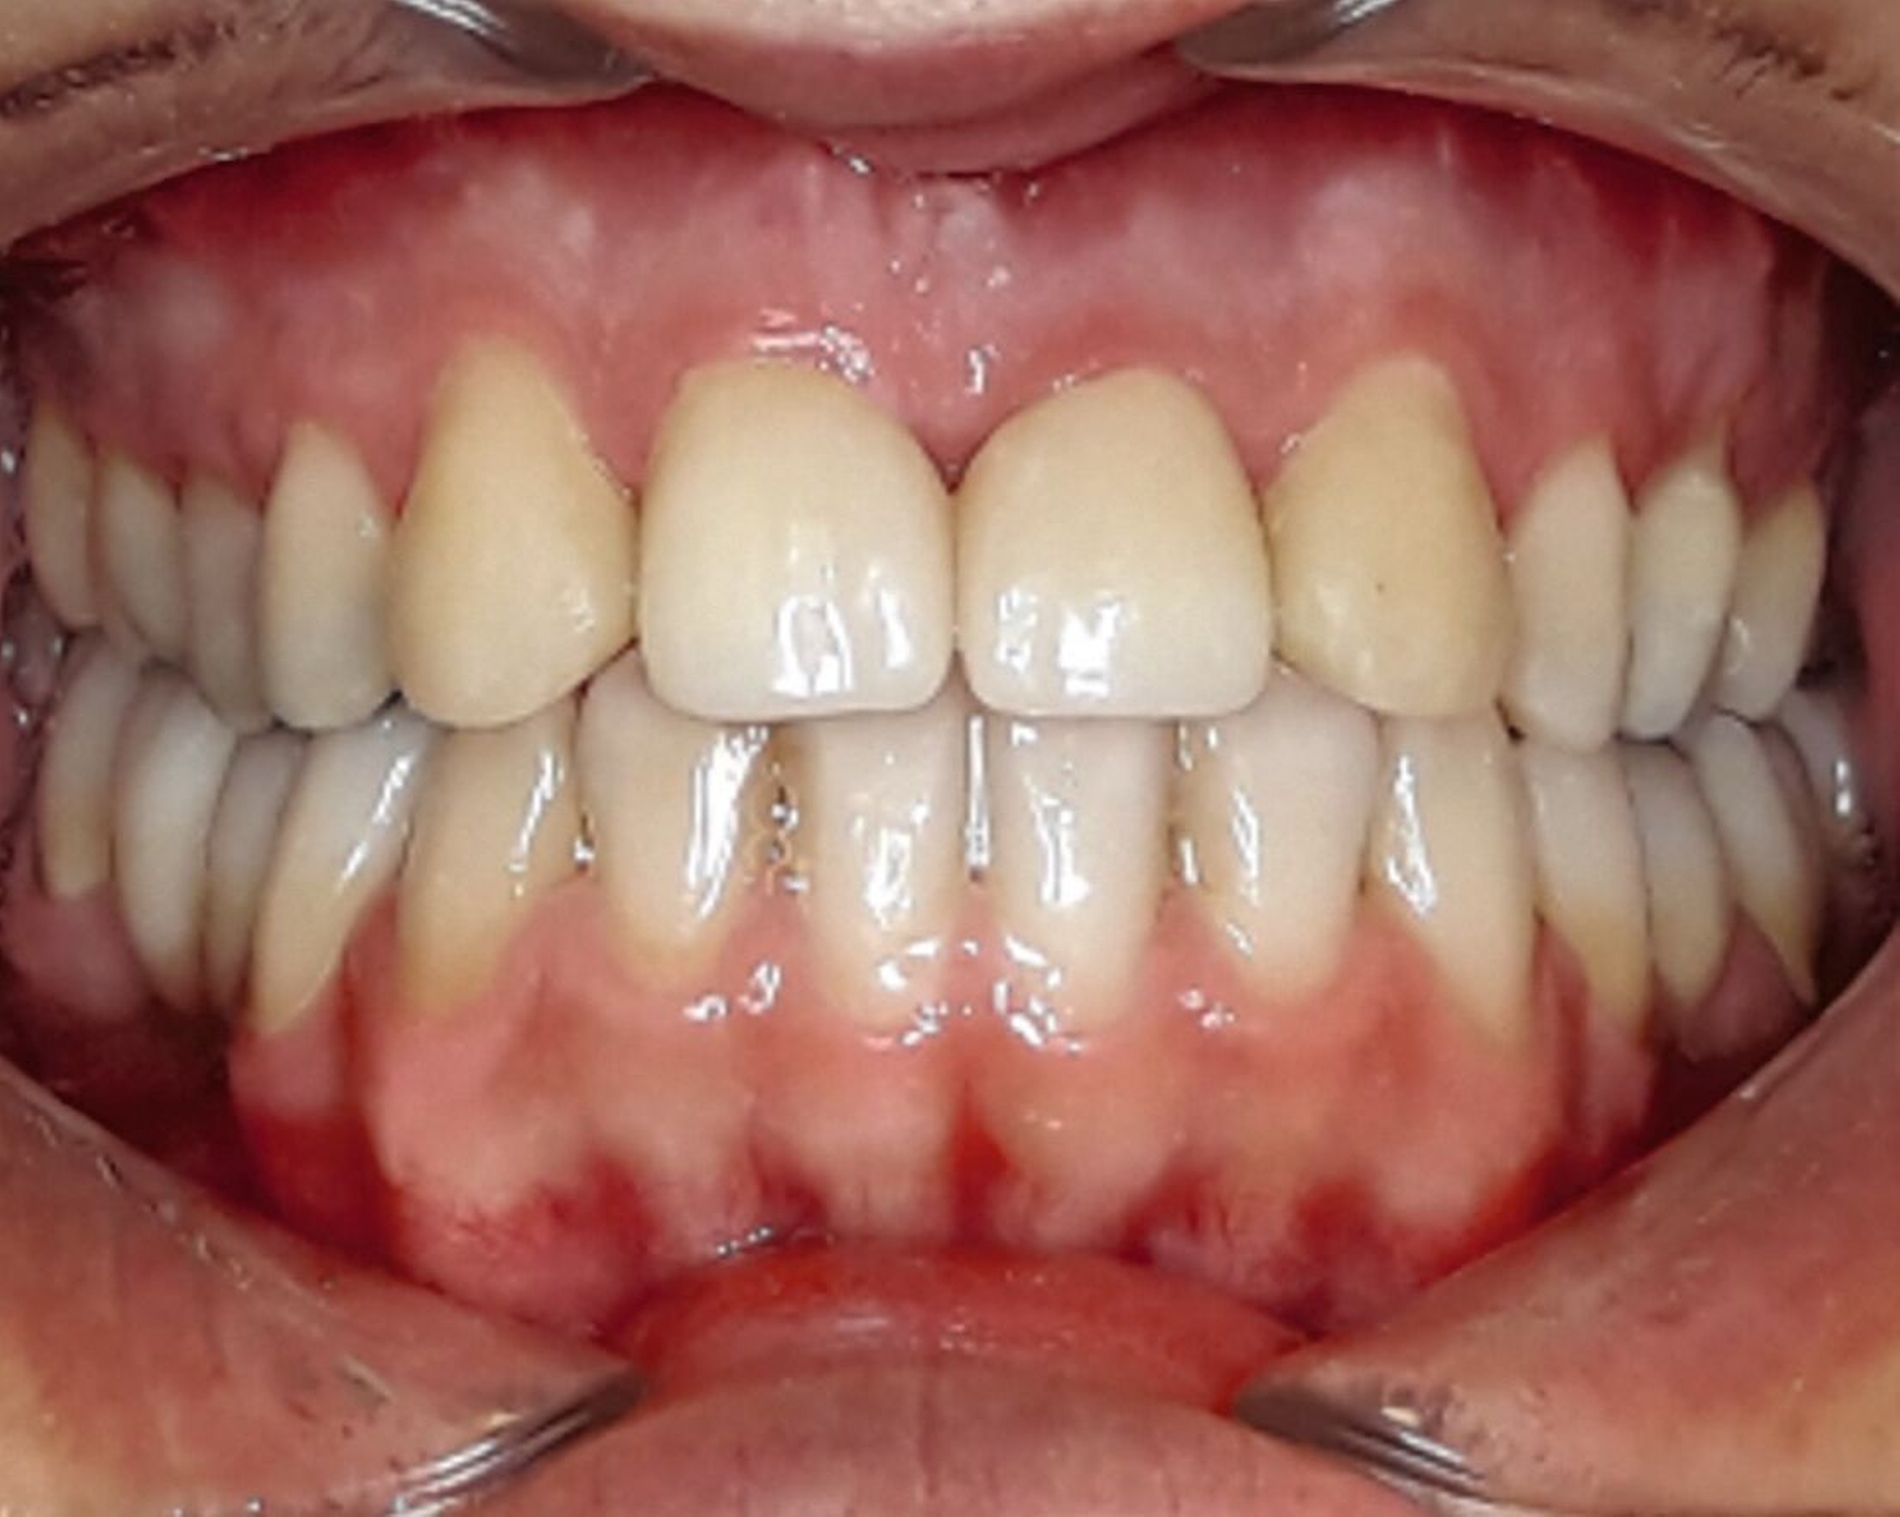

Der Hauszahnarzt versorgte die Zähne 12 und 22 mithilfe eines zuvor erstellten Wax-ups jeweils mit CAD/CAM-hergestellten Einzelkronen. Die Schaltlücken im Unterkiefer wurden mit Brücken geschlossen. Abschließend wurden im Unterkiefer ein festsitzender Retainer (33–43) eingesetzt und in beiden Kiefern zusätzlich Miniplastschienen zur Retention verwendet (Abbildungen 5 bis 7).